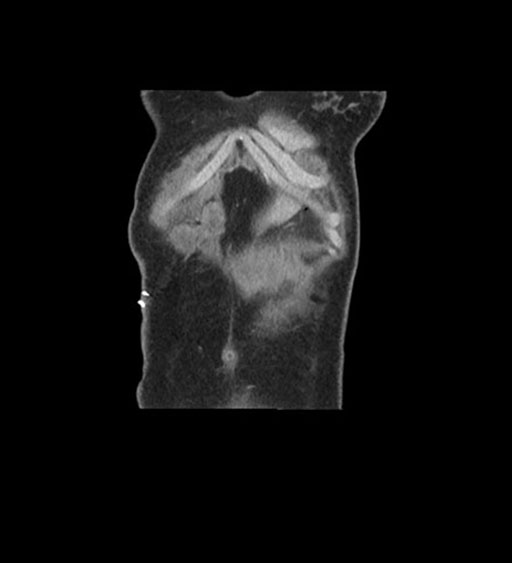

Coronal Arterial

Coronal Venous